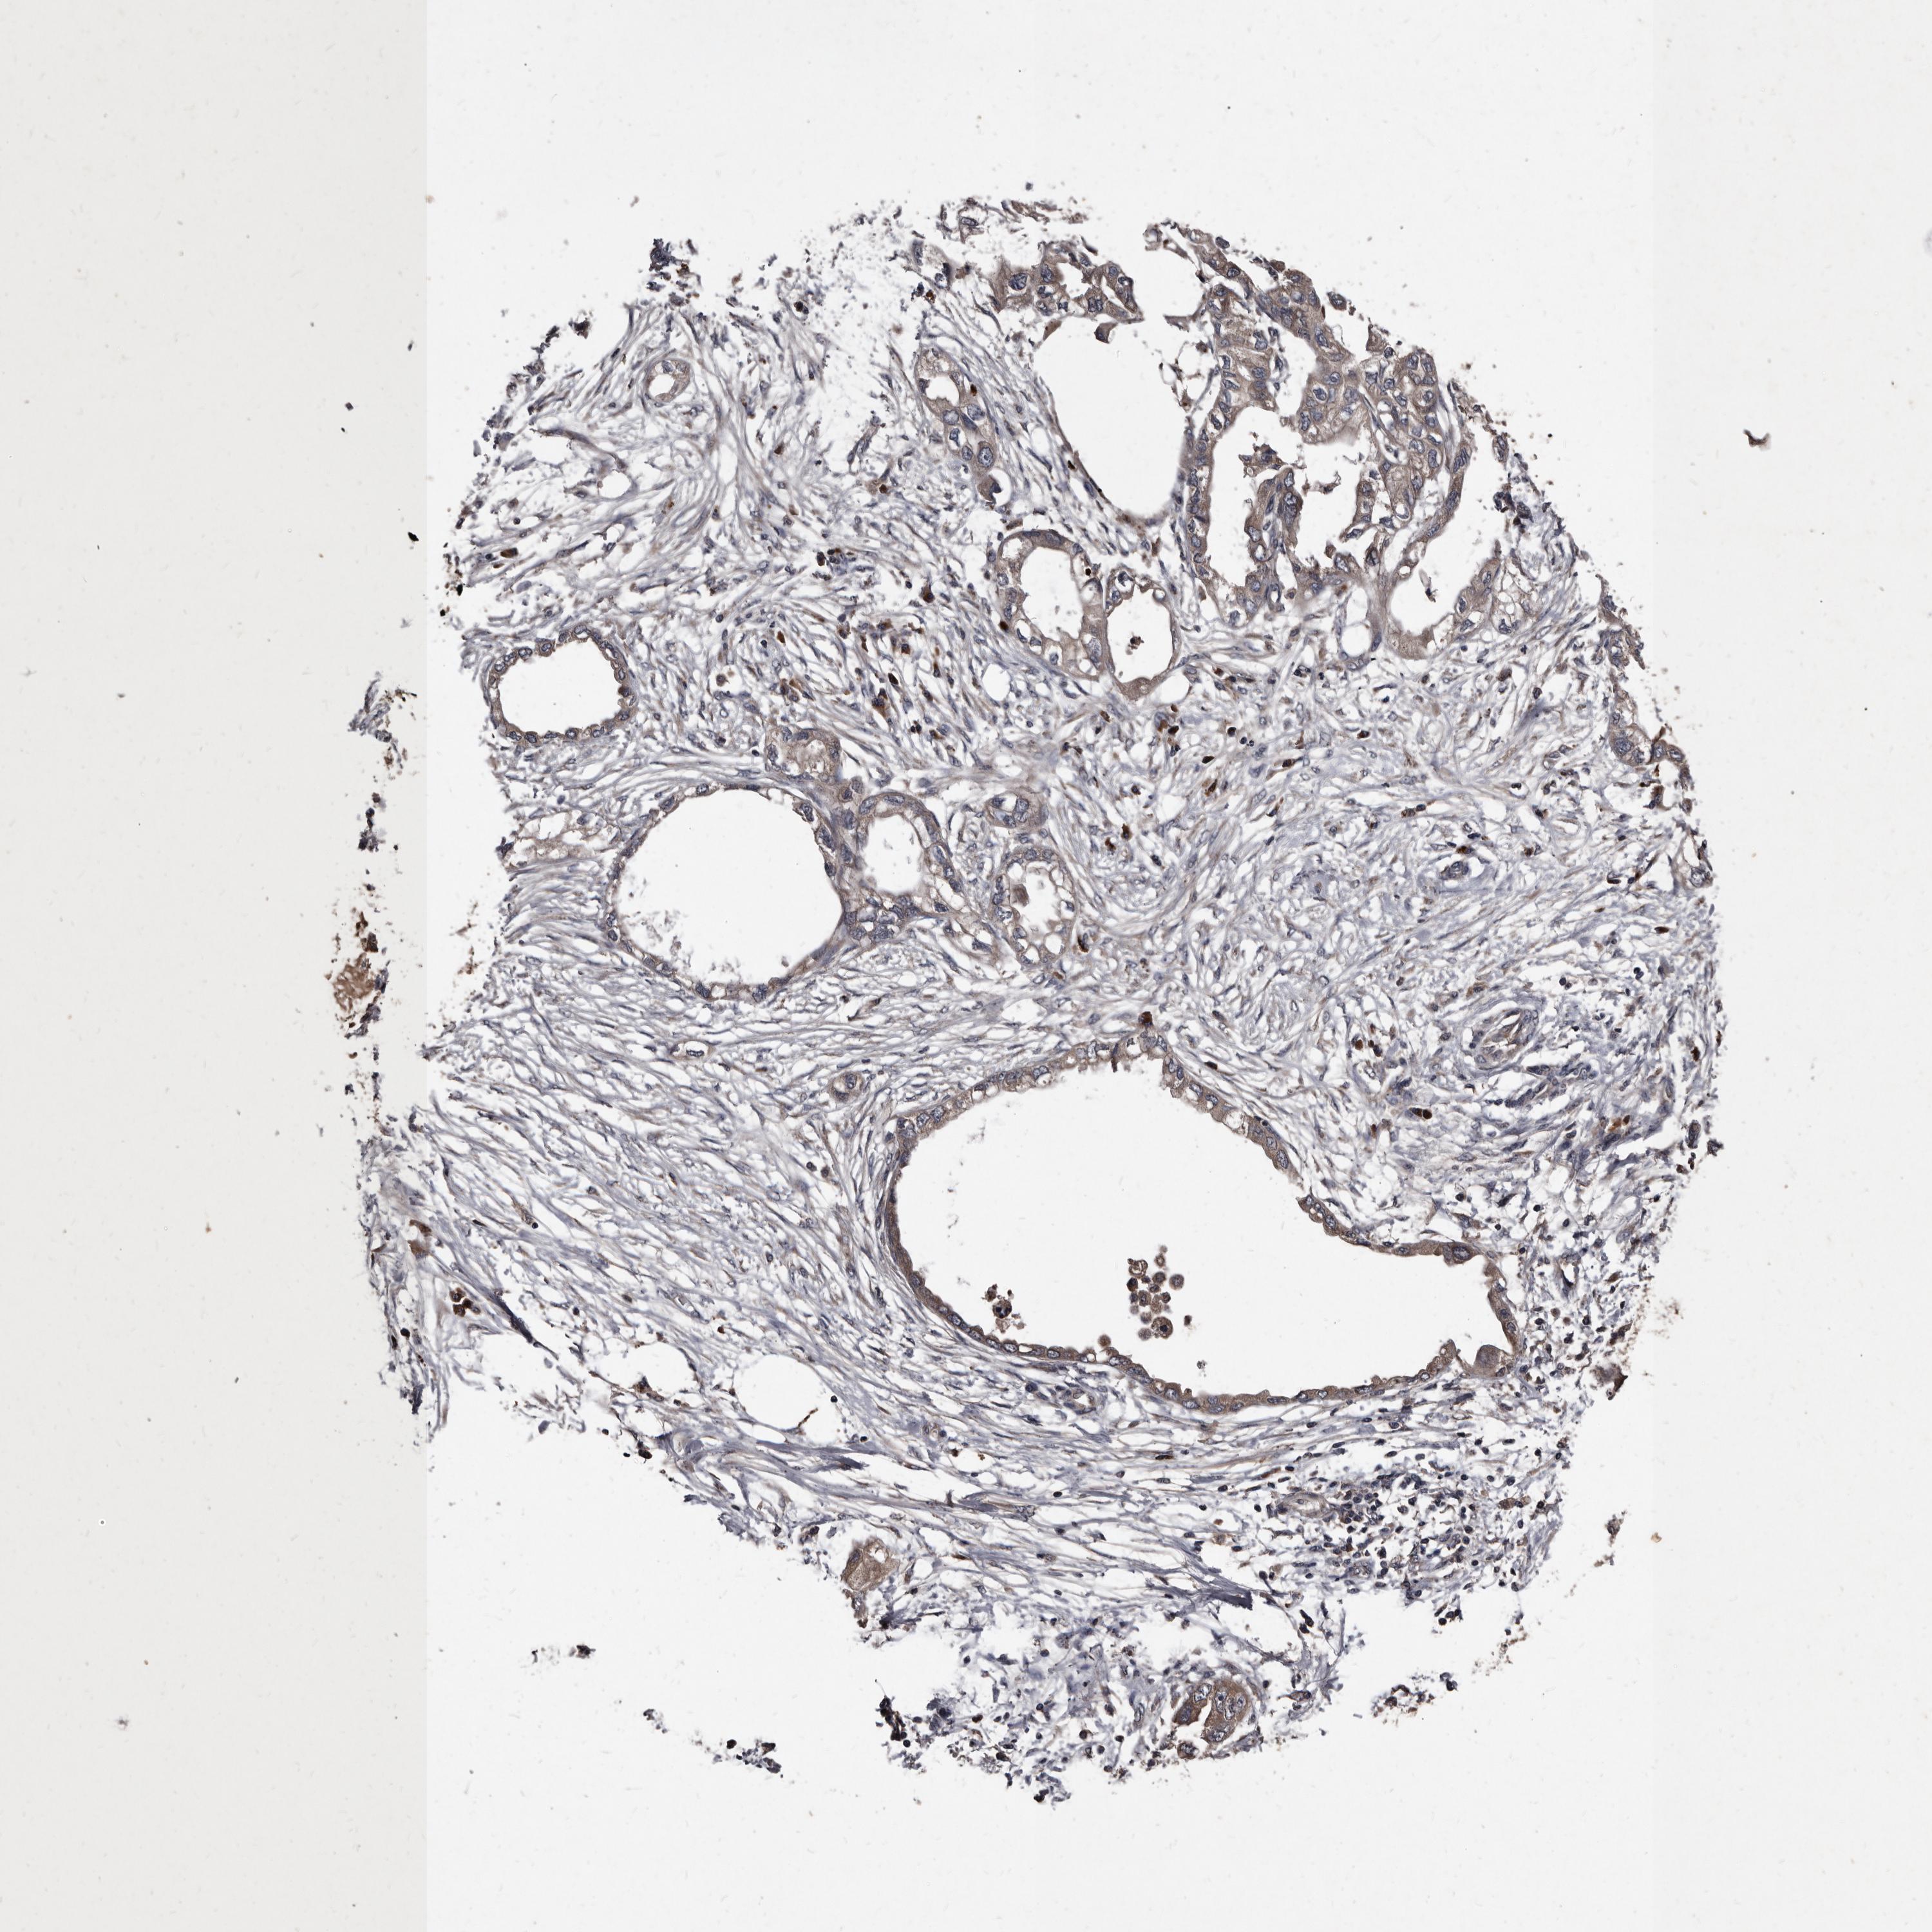

ENDOMETRIAL CANCER - Protein expressioni

A mouse-over function shows sample information and annotation data. Click on an image to view it in a full screen mode. Samples can be filtered based on level of antibody staining by selecting one or several of the following categories: high, medium, low and not detected. The assay and annotation is described here.

Note that samples used for immunohistochemistry by the Human Protein Atlas do not correspond to samples in the TCGA dataset.

Antibody stainingi

Antibody staining in the annotated cell types in the current human tissue is reported as not detected, low, medium, or high, based on conventional immunohistochemistry profiling in selected tissues. This score is based on the combination of the staining intensity and fraction of stained cells.

Each image is clickable and will lead to virtual microscopy that enables deeper exploration of all samples and also displays staining intensity scores, fraction scores and subcellular localization as well as patient and tissue information for each sample.

Antibody HPA029900

Staining

High

Medium

Low

Not detected

Intensity

Strong

Moderate

Weak

Negative

Quantity

>75%

75%-25%

<25%

None

Location

Nuclear

Cytoplasmic/membranous

Cytoplasmic/membranous,nuclear

Adenocarcinoma, NOS

Adenocarcinoma, metastatic, NOS